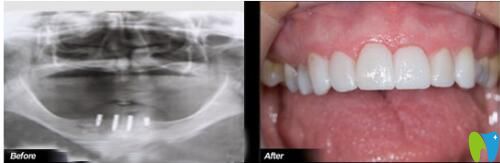

一位68歲朱老伯在沈陽歡樂口腔做完“一日得”種植牙說道:

“我先后換了5副活動(dòng)假牙,都抵不上4顆種植牙,14年前就開始掉牙,烤瓷牙沒法做,活動(dòng)假牙換了一回又一回,戴不牢;來到沈陽歡樂口腔時(shí),是在原有的假牙上鉆孔、固定、生根,做完當(dāng)天晚上就吃上大螃蟹了!”

68歲叔叔在歡樂仁愛口腔做完種植牙前后對比照